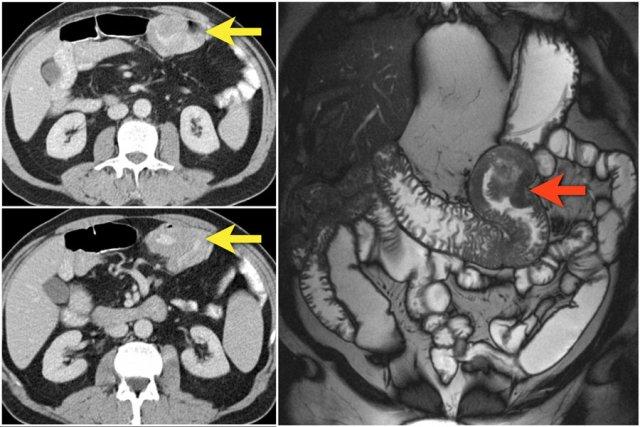

Hãy quan sát ảnh CT tái tạo mặt phẳng coronal.

Sau đó tiếp tục đọc.

Các dấu hiệu hình ảnh:

- Tổn thương hẹp lòng tá tràng do ung thư biểu mô tuyến (mũi tên vàng).

- Không thể phân tách khỏi tụy (mũi tên đỏ).

- Giãn tá tràng trước chỗ hẹp.

Đây là một ví dụ khác về ung thư tá tràng biểu hiện dưới dạng dày thành không đều ở đoạn xa tá tràng (các mũi tên).

Các hình ảnh cho thấy một khối hình vòng ngắn gây tắc nghẽn ở hỗng tràng (mũi tên vàng) kèm hạch bạch huyết to (mũi tên đỏ).

Kết quả giải phẫu bệnh xác nhận là ung thư biểu mô tuyến.

Chuỗi xung T1W sau tiêm thuốc tương phản từ có fat-sat (trái) và chuỗi xung T2W (phải) cho thấy một khối gây tắc nghẽn ở hỗng tràng với bờ dạng vai (mũi tên).

Có giãn ruột trước chỗ hẹp.

Các hình ảnh phía trên cho thấy một khối hình vòng ở đoạn gần hỗng tràng có tăng hấp thu FDG (mũi tên vàng).

Các hình ảnh MRI phía dưới cho thấy cùng khối hỗng tràng đó với bờ dạng vai và hạch to mạc treo (mũi tên đỏ), phù hợp với ung thư biểu mô tuyến.